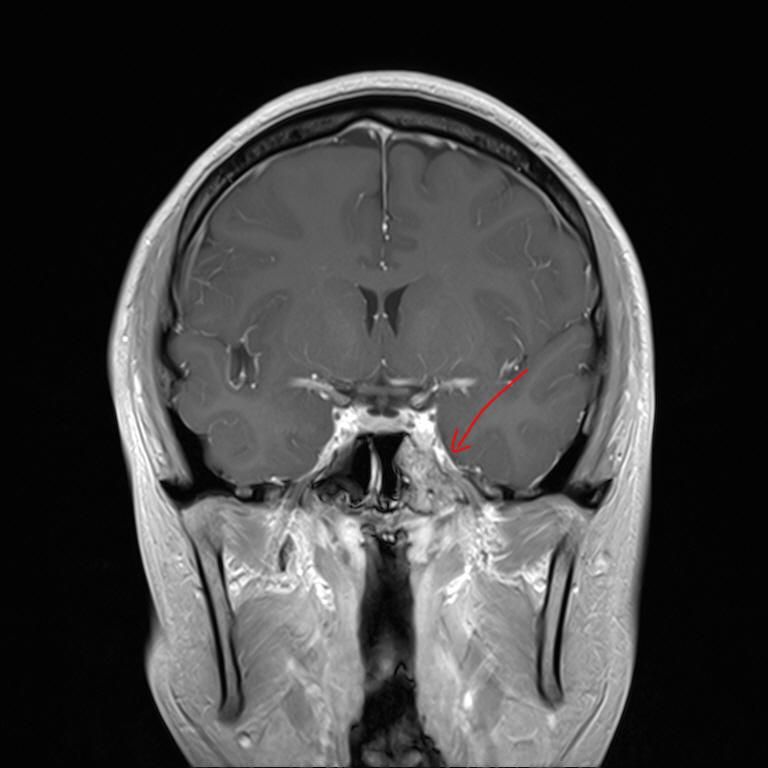

mri 사진을 봤을 때 정확히 어디가 막힌 걸까요? 그리고 치료는 할 수 있는 걸까요???

• 1번 째 사진

올려주신 영상 관련 보다 더 자세한 분석 원하시면 영상의학과 전문의한테 물어보셔야 해요

말씀하신 증상 관련 답변 드리자면 15년동안 지속된 귀와 코 사이 막힘 증상은 이관(유스타키오관) 기능 장애일 가능성이 높습니다. 진한 콧물을 강하게 들이마신 후부터 증상이 생겼다면, 이관이 분비물이나 압력 변화로 막히거나 손상되었을 가능성이 있습니다. 이관은 코 뒤쪽과 귀 중이를 연결하는 통로로, 막히면 귀먹먹함, 압력감, 울림 증상 등이 지속될 수 있습니다. MRI나 CT를 통해 이관 주변 구조(비인두, 부비동, 중이강 등)의 해부학적 이상을 더 정확히 확인해야 합니다.